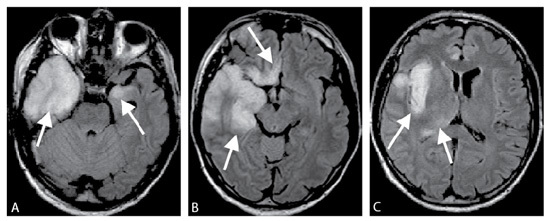

Un patient VIH stade SIDA présente des crises convulsives associées à une ataxie et des troubles visuels. Une IRM est réalisée, quelle est sa séquence, quel est le diagnostic?

IRM, séquence FLAIR.

Leucoencéphalite multifocale progressive car larges plages en hypersignal, confluentes de la substance blanche avec respect du cortex.

Un patient présente des troubles du comportement et des hallucinations auditives, une IRM est réalisée, quel est le diagnostic?

Méningoencéphalite herpétique.

Sur l’IRM T2 FLAIR on voit un hypersignal bilatéral prédominant à droite, temporal antérieur et interne associé à une atteinte élective du système limbique